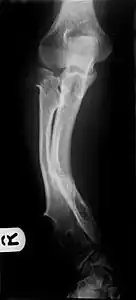

Multiple osteochondromas causing deformity of the forearm (shortening of the Radius with secondary bowing of the Ulna).